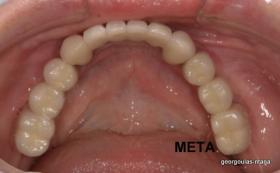

Η ασθενής αυτή είχε παλιές ακίνητες αποκαταστάσεις (γέφυρες) στην άνω γνάθο  κ μια κινητή προσθετική αποκατάσταση (μερική οδοντοστοιχία-"μασελάκι") στην κάτω γνάθο. Ήταν δυσαρεστημένη τόσο με την εμφάνιση όσο και με τη λειτουργία των δοντιών της καθώς παραπονιόταν ότι  είχαν εντονη κινητικότητα ενώ και οι προσθετικές τους εργασιές δεν ήταν σταθερές. Η πρόγνωση των δοντιών κρίθηκε φτωχή με αποτέλεσμα να μην είναι δυνατή η συμμετοχή τους σε μια νεα προσθετική αποκατάσταση με μακροχρόνια διάρκεια. Η ασθενής επιθυμούσε οι νέες αποκαταστάσεις να είναι σταθερές και ακίνητες.  Για το λόγο αυτό αποφασίστηκε η ολική αποκατάσταση της άνω κ κάτω γνάθου με ακίνητες επιεμφυτευματικές εργασίες. Στην αριστερή πλευρά της άνω γνάθου, λόγω μη επαρκούς οστού για την τοποθέτηση εμφυτευμάτων προηγήθηκε επέμβαση ανοιχτής  ανύψωσης ιγμορείου άντρου με τη χρήση πιεζοχειρουργικού μηχανήματος ώστε να δημιουργηθεί το κατάλληλο οστικό υπόστρωμα. Ακολούθησε σε επόμενο χειρουργείο η εξαγωγή των υπάρχοντων δοντιών κ η άμεση τοποθέτηση εμφυτεύματων (άμεση εμφύτευση) κ δύο μέρες μετά η τοποθέτηση προσωρινής εργασίας επί των εμφυτευμάτων (άμεση φόρτιση) με αποτέλεσμα η ασθενής να μη μείνει καθόλου χωρίς δόντια κ να είναι καλυμένη αισθητικά όσο καιρό διήρκησε η εργασία